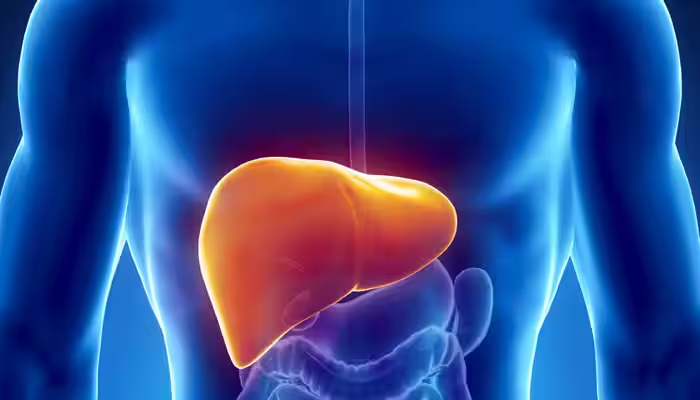

Ayurvedic remedies for liver diseases such as hepatitis, fatty liver, and jaundice.